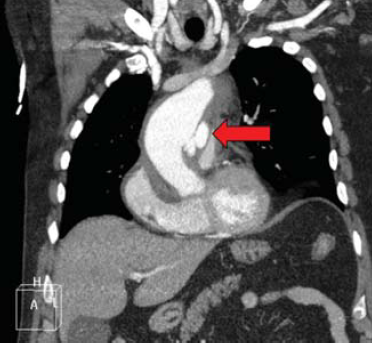

2. ábra.

PAU az aorta ascendensen.